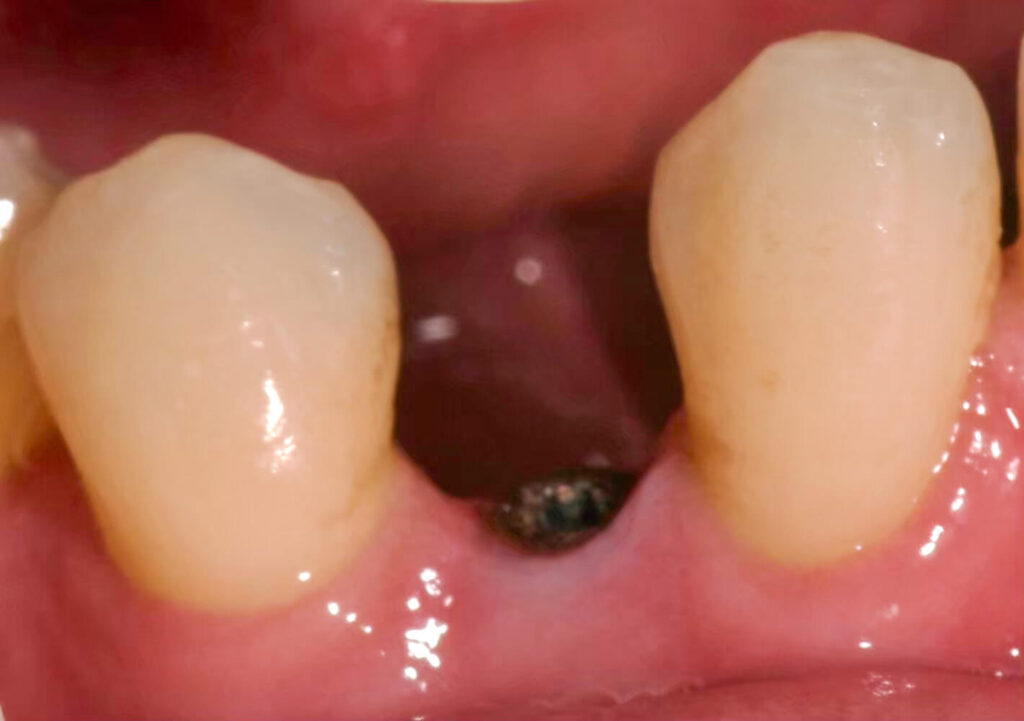

精準定位植牙,瞬間擺脫缺牙困擾

Before

After

A先生

A 先生的下排牙齒先天少一顆牙,導致周邊牙齒通通內擠過來,但仍然有一個小縫,而A先生一直以來的願望,就是能將這個縫補好。

雖然看起來是一個縫,但裡面的空間其實很小,因為除了上面牙齒傾倒,還要考量內部的骨頭空間,因此不是單純肉眼說可以就可以的。

A先生前後在其他間診所評估後,但因為空間狹小提升植牙難度,被拒絕了好幾次。

來到京鼎牙醫診所諮詢後,發現有X-Guide藍光導航機,且林建佑院長相當重視精准度,一顆植牙也會使用導航,提高成功率、讓患者用得長久!

後來手術前先用斷層確認骨頭狀態,來X-Guide藍光導航機來輔助植牙,有GPS定位找出適合的角度植牙,就算是小空間也能提升精准度,也減少患者要搭配其他療程的痛苦。

由於先天缺牙使用越久、年紀越大,對於咬合影響更劇烈,因此不論是後天缺牙還是先天少牙都會影響,因此先天缺牙也建議好好看待。